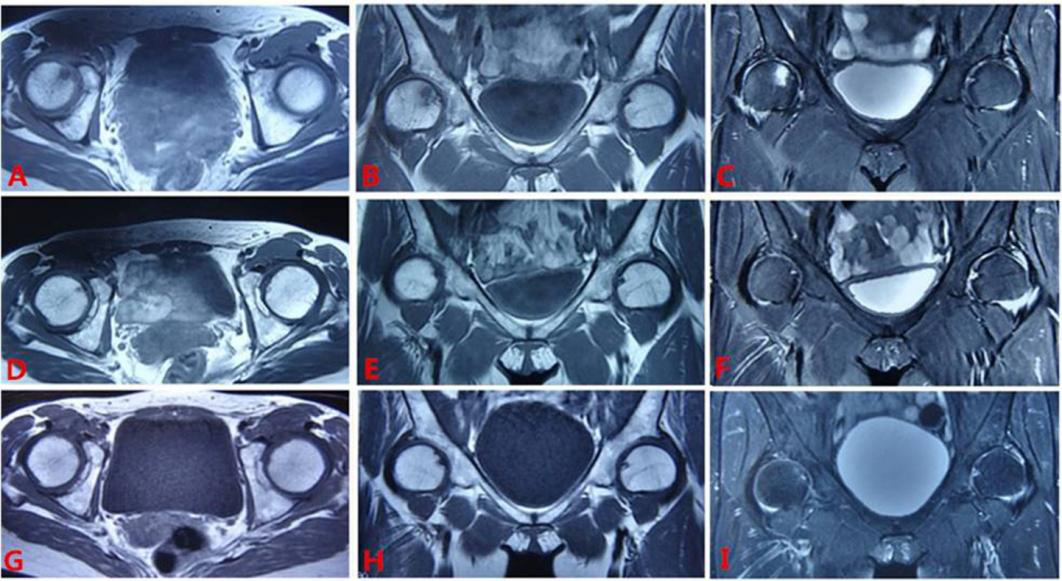

病例:女 46岁,右侧Ⅱ期,治疗9个月痊愈。

治疗前A-C,MRI右侧大面积异常信号,见双线征;治疗9个月D-F:异常信号消失,患者痊愈。愈后2年随访G-I:MRI信号正常。

Case: A 46 year old female, right phase II, recovered after 9 months of treatment. Before treatment, A-C, MRI showed a large area of abnormal signal on the right side, with a double line sign; 9-month treatment for D-F: Abnormal signals disappeared and the patient recovered. Follow up for 2 years after recovery: G-I: MRI signal is normal.